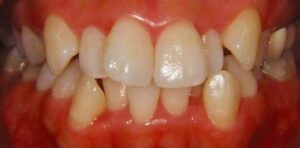

無料メール相談2 (矯正は何歳から始めたら良いですか?)

今まで、多くの方々に無料でメール相談をしてきました。その中から良くある相談を紹介しています。 「矯正は何歳から始めたら良いですか?」 矯正が必要な歯並びを不正咬合(ふせいこうごう)と言いますが、その種類によって時期・開始年齢は異なります。最 […] 本文を読む